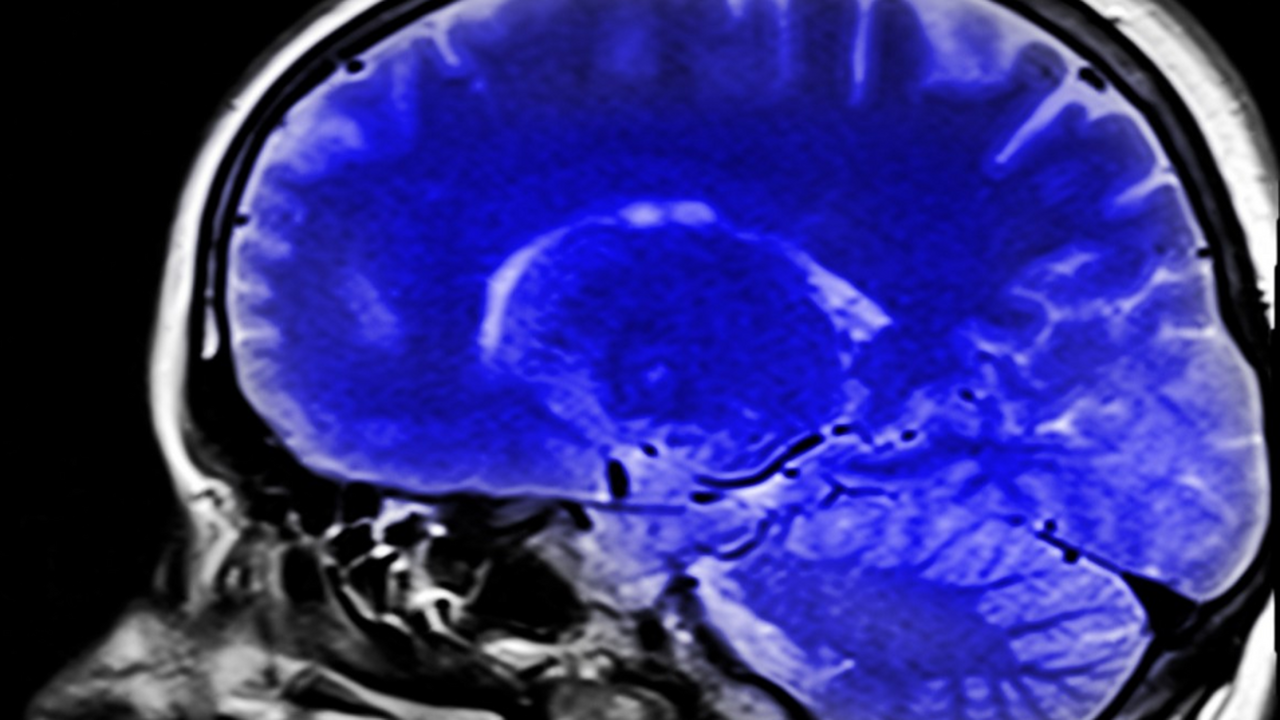

Исследование: компульсивное поведение может быть связано с воспалением мозга

Новое исследование Технологического университета Сиднея показало, что компульсивное поведение может быть связано не только с вредными привычками и потерей самоконтроля, но и с воспалением головного мозга. Ученые предположили, что нейровоспаление способно влиять на принятие решений и провоцировать повторяющиеся действия, даже если они приводят к негативным последствиям. Перевод исследования, которое было опубликовано в журнале Neuropsychopharmacology, сделал proulyanovsk.ru.